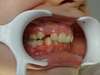

Intrabuccale face - Avant traitement 1 (25-01-2021) - 2